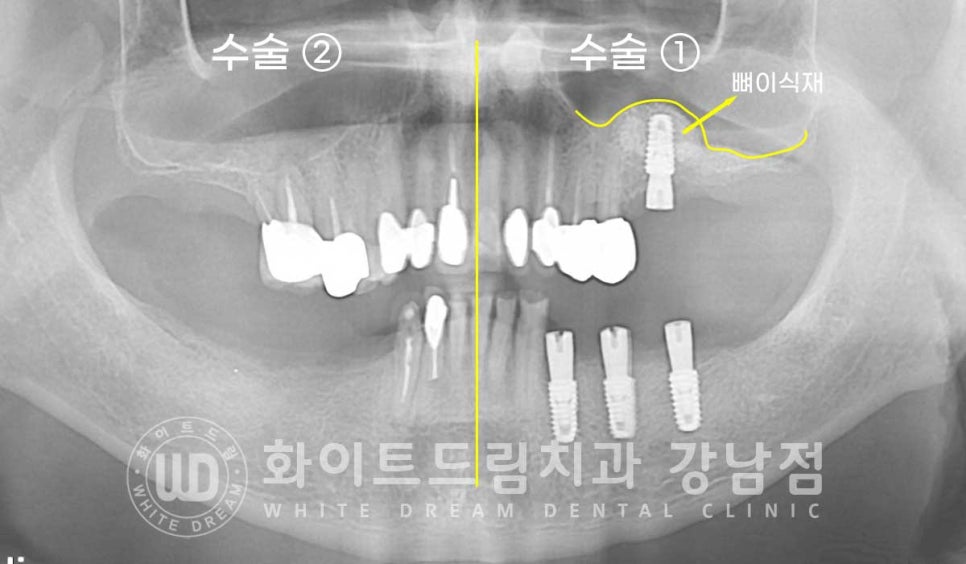

환자분은 식사의 문제로 왼쪽, 오른쪽으로 나누어 수술을 진행하였고

양쪽 상악 어금니는 안내드린 대로 lateral, 측방 접근법인 상악동 거상술을 동반하여

대량의 뼈이식 후 임플란트를 식립했습니다.

환자분의 상악동 거상 술 전의 잇몸뼈 높이와 거상 후를 비교해 보면

한눈에 어떤 부위에 대량의 뼈이식이 진행됐는지 확인하실 수 있을 겁니다.

노란색 점선이 초기 환자분의 잇몸뼈 높이이며, 거상 후 하늘색 선 만큼 상악동이 올라갔고

그 사이에 하얗게 보이는 뼈이식재가 들어간 것이 확인됩니다.

이후 5개월의 회복 기간을 가진 후 임플란트 최종 보철 제작과

교합 체크 과정인 마무리 단계를 거쳐 치료를 완료하게 되었습니다.